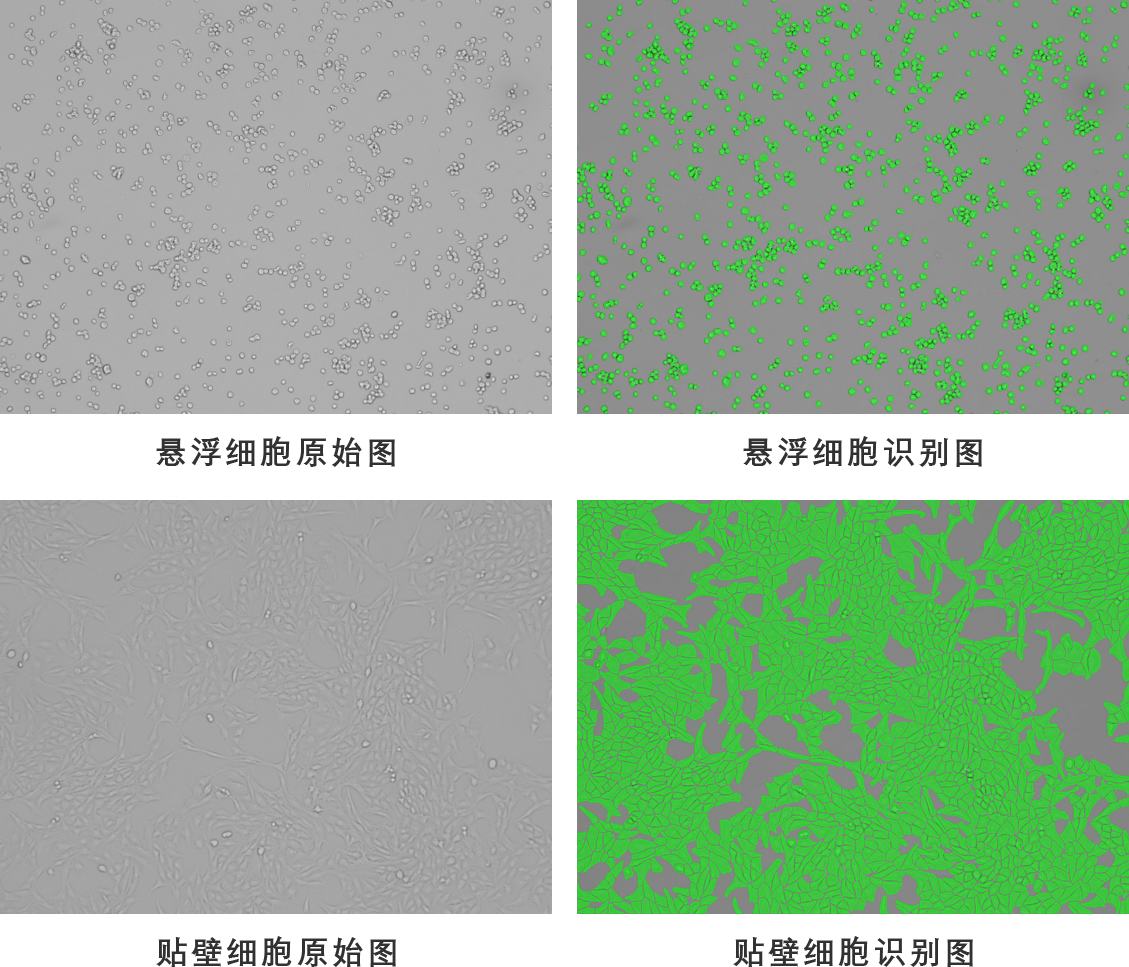

廣州博大博聚科技有限公司是一家集研發、生產、銷售為一體的國家高新技術企業。公司專業致力于細胞學分析儀器的研發和制造,高度重視自主知識產權的積累,于2013年推出自主研制的全自動細胞計數儀,并獲得2014年度的“中國創新設計紅星獎”。

多年來,公司秉承自主研發,專業專注的精神,以“細胞計數標準化”為原則,在細胞計數分析平臺上不斷創新和積累,形成了成熟的技術體系,為科研人員提供智能、標準、可靠的細胞分析產品和完善的技術服務。